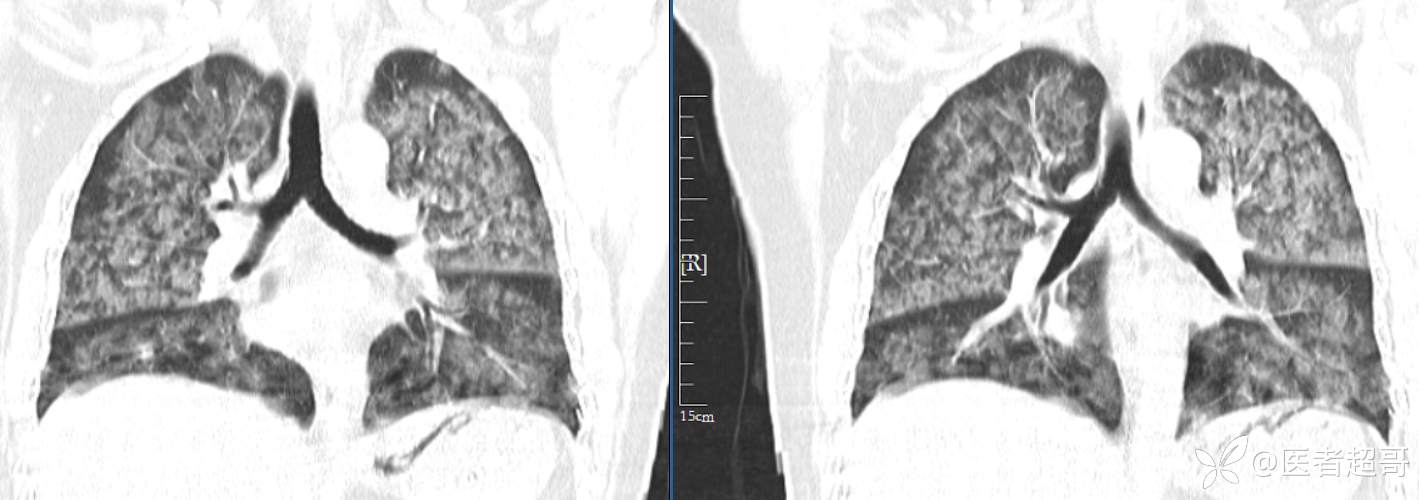

【影诊笔记574】胸痛就诊检查,发现双肺多发高密度,请赏析!

患者性别:女

患者年龄:47岁

主诉:胸痛就诊

简要病史:因“胸痛就诊”,行冠脉CTA检查,数小时后出现高热,伴畏寒寒战、气喘,暗红色泡沫样痰。

急性肺水肿 (17)